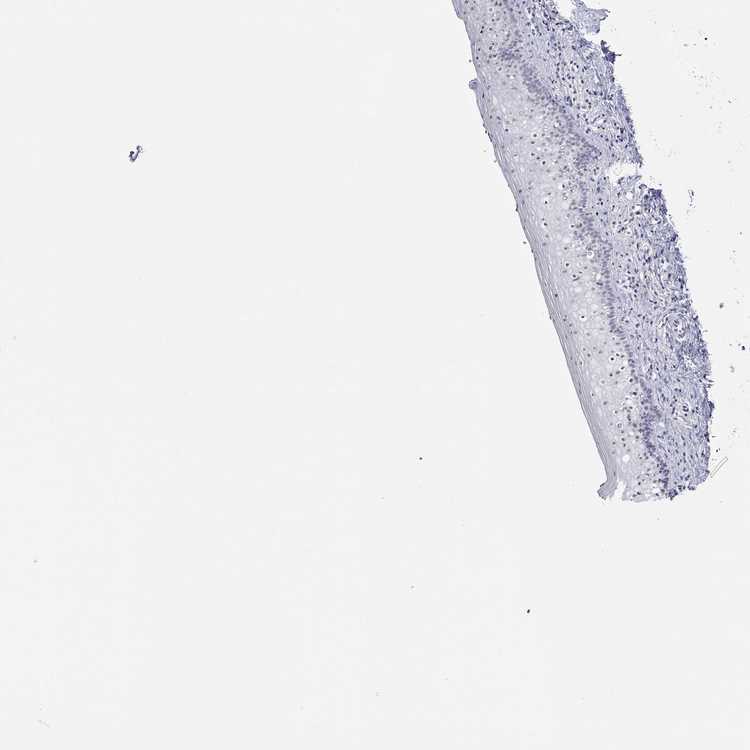

TISSUE PRIMARY DATA VAGINA Show tissue menu

VAGINA - Antibody stainingi

Antibody staining in the annotated cell types in the current human tissue is reported as not detected, low, medium, or high, based on conventional immunohistochemistry profiling in selected tissues. This score is based on the combination of the staining intensity and fraction of stained cells.

Each image is clickable and will lead to virtual microscopy that enables deeper exploration of all samples and also displays staining intensity scores, fraction scores and subcellular localization as well as patient and tissue information for each sample.

Antibody HPA035530Antibody HPA035531

Squamous epithelial cells LowLow